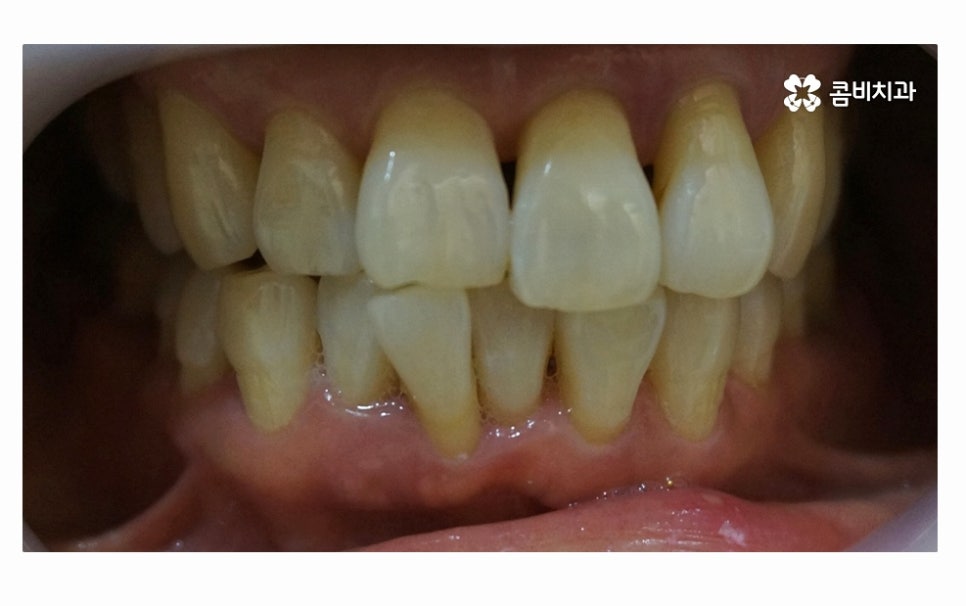

사진에서 보시는 것처럼 치아 사이에 빈 공간도 많고

잇몸이 내려앉아서 치아의 하단부도 많이 드러난 상태인데

치아를 잇몸이 제대로 감싸주지 못하고 이렇게

내려앉게 될 경우 치아도 많이 시리게 되고

치주염이 심해지는 단계에서는 치아가 흔들려서

식사도 제대로 하지 못할 정도로 어려움을 겪게 되실 수 있어요.